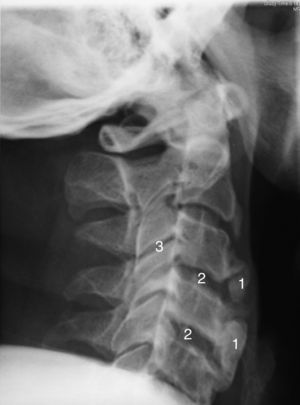

Tras valorar su evolución radiológica cervical en los últimos 5 años, de este paciente, se observa un aumento de las dimensiones de los osteofitos y de la osificación del ligamento cervical anterior afectando a varias vértebras contiguas (figs. 1 y 2), lo que podría explicar una causa extrínseca de la disfagia. También cabe destacar otras características radiológicas como son la preservación relativa del espacio intervertebral y la ausencia de afectación de las articulaciones apofisiarias.

En la TAC cervical se constató la osificación del ligamento longitudinal anterior y osteofitos anteriores, con afectación fundamentalmente en la columna cervical alta (C2-C4), que condiciona desplazamiento anterior del tracto aerodigestivo. No se constató la afectación de las articulaciones interapofisarias.